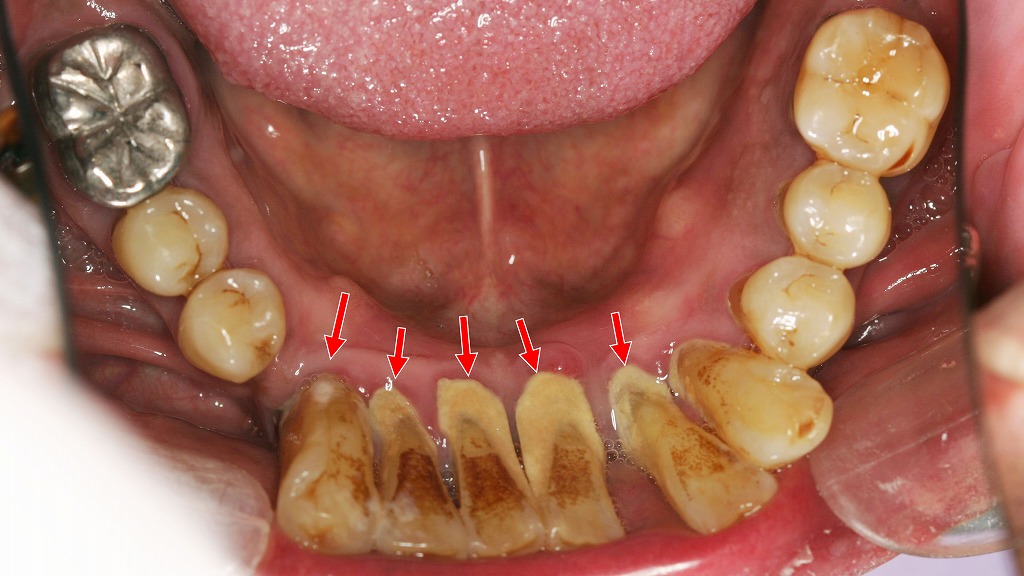

歯周病の進行によって起こるフレアアウト(前歯の倒れ込み)症例

下顎前歯の舌側に大量の歯石が付着し、歯周病が進行している状態です。

歯を支える骨や歯周組織が弱くなると、前歯は内側からの舌の圧や噛み合わせの力に耐えられず、徐々に前方へ倒れ込む「フレアアウト」を起こします。

フレアアウトは見た目の問題だけでなく、歯周病のさらなる悪化や噛み合わせの不調を招くため、早期の歯周治療と歯石除去が重要です。